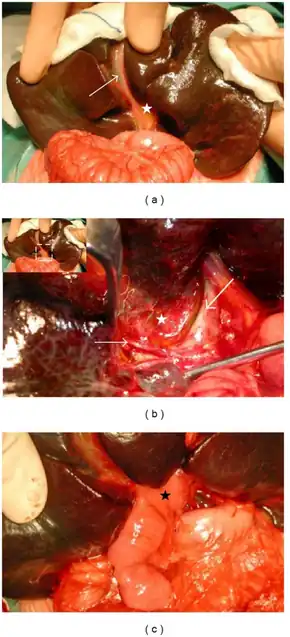

| Intraoperative view of complete extrahepatic biliary atresia[1] | |